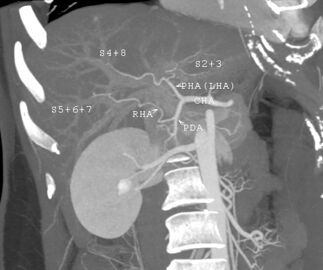

With the recent advances of noninvasive imaging, living liver donors usually have to undergo imaging examinations for liver anatomy to decide if the anatomy is feasible for donation. The evaluation is usually performed by multidetector row computed tomography (MDCT) and magnetic resonance imaging (MRI). MDCT is good in vascular anatomy and volumetry. MRI is used for biliary tree anatomy. Donors with very unusual vascular anatomy, which makes them unsuitable for donation, could be screened out to avoid unnecessary operations.